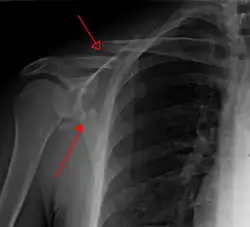

Pfannenrandbruch

Pfannenrandbrüche sind fast immer Folge einer Schulterluxation und entsprechen knöchernen Ausrissen der Gelenkkapsel. Ein typisches Beispiel und die häufigste Glenoidfraktur ist die knöcherne Bankart-Läsion, die den knöchernen Ausriss am vorderen Pfannenrand bei vorderer Schulterluxation bezeichnet. Beim Pfannenrandabbruch ist immer auch die Gelenklippe (Labrum glenoidale) gerissen und meist auch die Gelenkkapsel gerissen. Ohne operative Fixierung des abgerissenen Pfannenrandes kann eine chronische Instabilität des Glenohumeralgelenkes resultieren.[4] Die Refixierung erfolgt meist durch Kleinfragment-Zugschrauben über einen vorderen oder hinteren operativen Zugang.